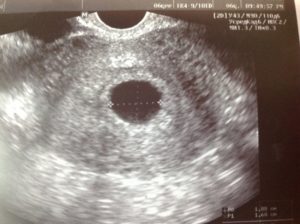

Также случается противоположная анэмбрионии картина, когда ультразвуковое исследование определяет одно плодное яйцо и два эмбриона в нем.

Речь идет о многоплодной беременности, которую будет видно, где-то начиная с шести недель гестации.

Данные медицинской литературы дают ответ на вопрос: «может ли в плодном яйце два эмбриона одновременно расти и развиваться?». Да, конечно могут, но явление достаточно редкое.

Что касается ультразвуковой визуализации развивающегося внутриутробно человека, то на стадии 4 акушерских недель возможно увидеть только лишь плодное яйцо. В период 5-6 акушерских недель возможно зарегистрировать сердцебиение эмбриона. Отчётливо эмбрион в виде буквы С может быть идентифицирован в матке на уровне 7-8 недель.

Одно плодное яйцо и два эмбриона. Конечно же, в плодном яйце развитие двух эмбрионов может быть. При таком обстоятельстве на свет появятся монозиготные близнецы. В народе их называют однояйцевыми. Данные малыши являются абсолютно идентичными.

Они развиваются путём оплодотворения одним сперматозоидом одной яйцеклетки. Сформированная зигота начинает делиться с определённым нюансом. В процессе дробления образуется не один эмбриона, как обычно, а два.

Данные крохи являются копиями друг друга, имеющие одинаковый генетический материал.